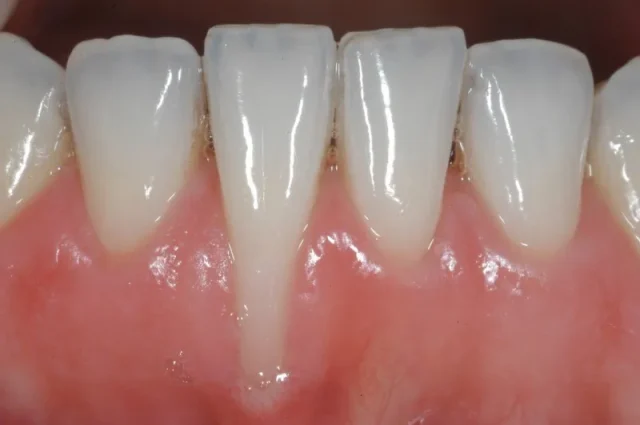

Răng Mòn và Viêm Lợi

Khi răng có dấu hiệu dài ra, nguyên nhân thường liên quan đến tình trạng tụt nướu hoặc mòn men răng. Điều này khiến phần chân răng lộ ra, làm răng trở nên nhạy cảm hơn khi ăn uống nóng lạnh. Đồng thời, tụt nướu cũng tạo điều kiện cho vi khuẩn tích tụ, dễ dẫn đến viêm lợi, chảy máu chân răng và nếu kéo dài có thể tiến triển thành bệnh nha chu ảnh hưởng đến độ chắc khỏe của răng.